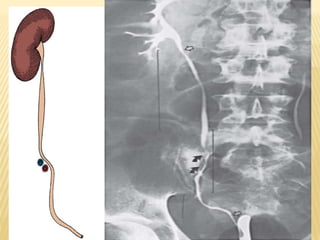

Sites of ureteral narrowing:

-Ureteropelvic junction.

-Junction as the ureter crosses the iliac

vessels.

URETER ANATOMY Sites ofureteral narrowing: -Ureteropelvic junction. -Junction as the ureter crosses the iliac vessels. -Ureterovesical junction. :